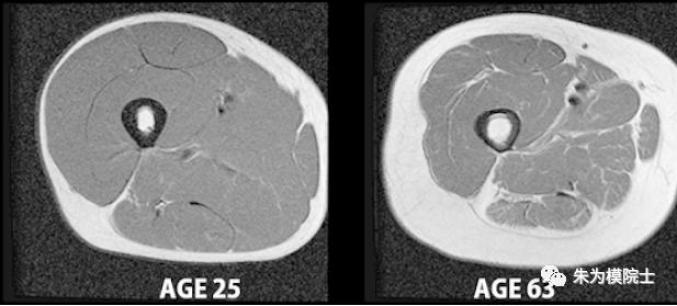

随着年龄增加,肌肉面积(上图-A)和肌纤维数量(上图B)都会减小和减少;下图为25岁和63岁男性的大腿肌肉横断扫描照片(外围白色为脂肪,里面灰色为肌肉,中间黑白为骨头),也证明了岁月的无情。

但可喜的是运动可以有效地缓减衰老的速度(上中下图分别为40岁男性铁人三项运动员,70岁久坐不动男性和70岁男性铁人三项运动员大腿肌肉横断扫描照片)- 生命在于运动!老年人和女性都应该定期做力量训练。为什么叫肌肉为“好体重”呢?这是因为肌肉可以帮助身体清理多余的血糖,肌肉体积增加可以帮助人的基础代谢率提高,力量大了,脚和身板硬了,人也愿意动起来,有氧能力也有所提高。另外,虽然有些力量训练属于无氧运动,但锻炼后的肌肉细胞水平的恢复并不是马上停止,相反,这类恢复活动可以延续较长时间,因为这些恢复活动需要能量支持,力量训练后的卡路里消耗也是相当可观的,和运动时的卡路里消耗加在一起,力量训练的耗能功能绝不亚于有氧运动。